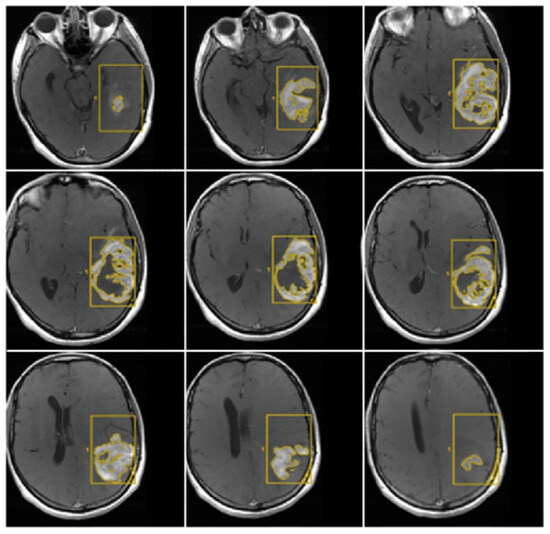

3.2. Quantitative Analysis